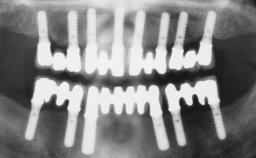

Immediate Loading of Six Implants in the Maxilla and Final Restoration with a Full-Arch Gold/Ceramic FDP Involving the Concept of Tilted Implants

A 61-year-old male patient with a failing fixed maxillary rehabilitation and a fixed mandibular rehabilitation requested a new fixed maxillary rehabilitation. The patient was wearing a temporary metal-reinforced maxillary bridge inserted two years before the consultation. He reported that his previous dentist did not want to insert a definitive framework because he considered the residual teeth to have a negative prognosis. The patient reported a history of recurrent caries and endodontic complications as the main reason for the previous extractions. The anamnesis was negative for periodontal disease and bruxism. The patient’s chief compliant was the mobility of his maxillary prosthesis, which needed to be re-cemented frequently, and discomfort during chewing.Moreover, the patient was not satisfied with the esthetic appearance of his maxillary teeth, which he found too long. The patient asked for a stable and comfortable fixed maxillary rehabilitation and firmly rejected any removable solution.

# of Implants 6

Type of Implants One-Piece|Reduced-Diameter

Defining Characteristics Fully edentulous upper jaw to be rehabilitated with four or more implants

Modality Fixed hybrid bridge on 5+ implants

Bone Volume Deficient horizontally, allowing simultaneous augumentation

Defining Characteristics Fully edentulous upper jaw to be rehabilitated with an implant-borne fixed dental prosthesis

Loading Protocol Immediate